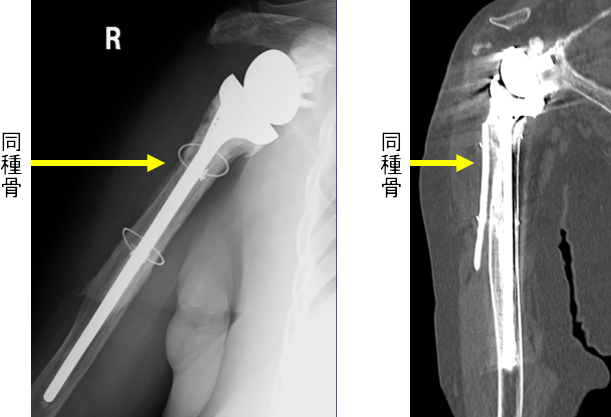

Therefore, we use an allogeneic tibial bone graft.

In this patient, an allograft from the tibia was used.

By fixing the allograft to the humerus with wires, we ensure that the bone split closes properly.

Immediate postoperative image

The allograft remains fixed to the humerus even after 3 years, and the stem is firmly secured within the humerus.